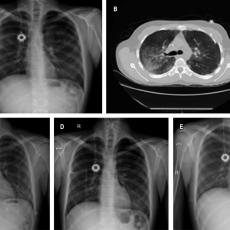

Síndrome de fuga aérea torácica por enfermedad de injerto contra huésped posterior a trasplante alogénico de médula ósea

Montero-Ureña, Raúl Enrique1; Contreras-Rodríguez, Felipe de Jesús2; Márquez-Barajas, Jesús1; Anaya-Gómez, Francisco José1; García-González, Luis Alberto1; Valdez-Rojas, Leonora1; Garnica-Vázquez, Johana Jazer1; Jiménez-Tornero, Jorge1; Díaz-Alba, Alexandra1; Luna-González, Cristina Alejandra1; Álvarez-González, Martha Georgina1; García-Valadez, Yunuen1; Solano-Genesta, Manuel1